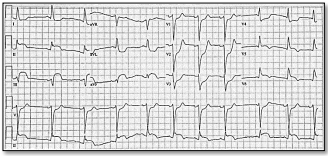

Um homem de 47 anos procura atendimento

médico de urgência com queixa de dor

torácica tipo aperto de início há

aproximadamente 40 minutos. Refere

histórico de Hipertensão Arterial Sistêmica

(HAS) e dislipidemia. Trouxe um

eletrocardiograma realizado há cerca de 30

dias, com bloqueio de ramo esquerdo. Após

realização de um novo ECG (mostrado a

seguir), qual é a conduta adequada?